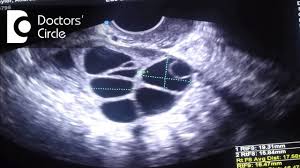

What Is The Ideal Size Of Mature Follicle For Infertility Treatment Dr Punyavathi C Nagaraj Youtube

A dominant follicle is a fluid filled structure in the ovary that grows big enough to release a mature egg around day 14 of a 28 day menstrual cycle or around a week prior to the midpoint of a cycle through the process of ovulation. Follicles in the ovary begin developing under the influence of a complex interplay of hormones and after several days one or occasionally two become dominant non dominant follicles atrophy and die. Follicle ka matalab hindi me kya hai follicle क ह द म मतलब.

Usually approximately 10 graafian follicles begin to mature where one becomes a dominant follicle and the rest become atretic ovarian follicles after release of the ovum the remainder of the dominant follicle turns into a corpus luteum and finally into a scarred corpus albicans. भ रत त य ह र और म ल क द श ह वस त त. The dominant follicle releases an ovum or egg in an event called ovulation.